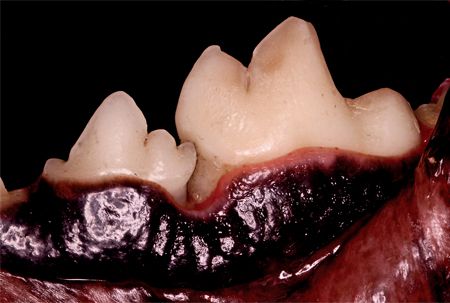

The root cause of periodontal disease is plaque that accumulates daily unless removed. Gingivitis occurs as a reaction to a plaqueladen biofilm. If the plaque is not disturbed, it solidifies into calculus (tartar). Calculus is rough compared with smooth enamel. This rough surface accumulates more plaque (Photo 1).

Photo 1: Plaque accumulating over rough calculus, causing gingival inflammation.